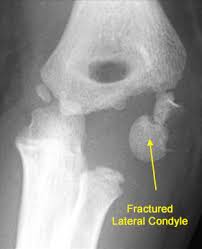

Elbow Fractures In Children An Overview Hss Edu

Elbow Fractures In Children An Overview Hss Edu from www.hss.edu